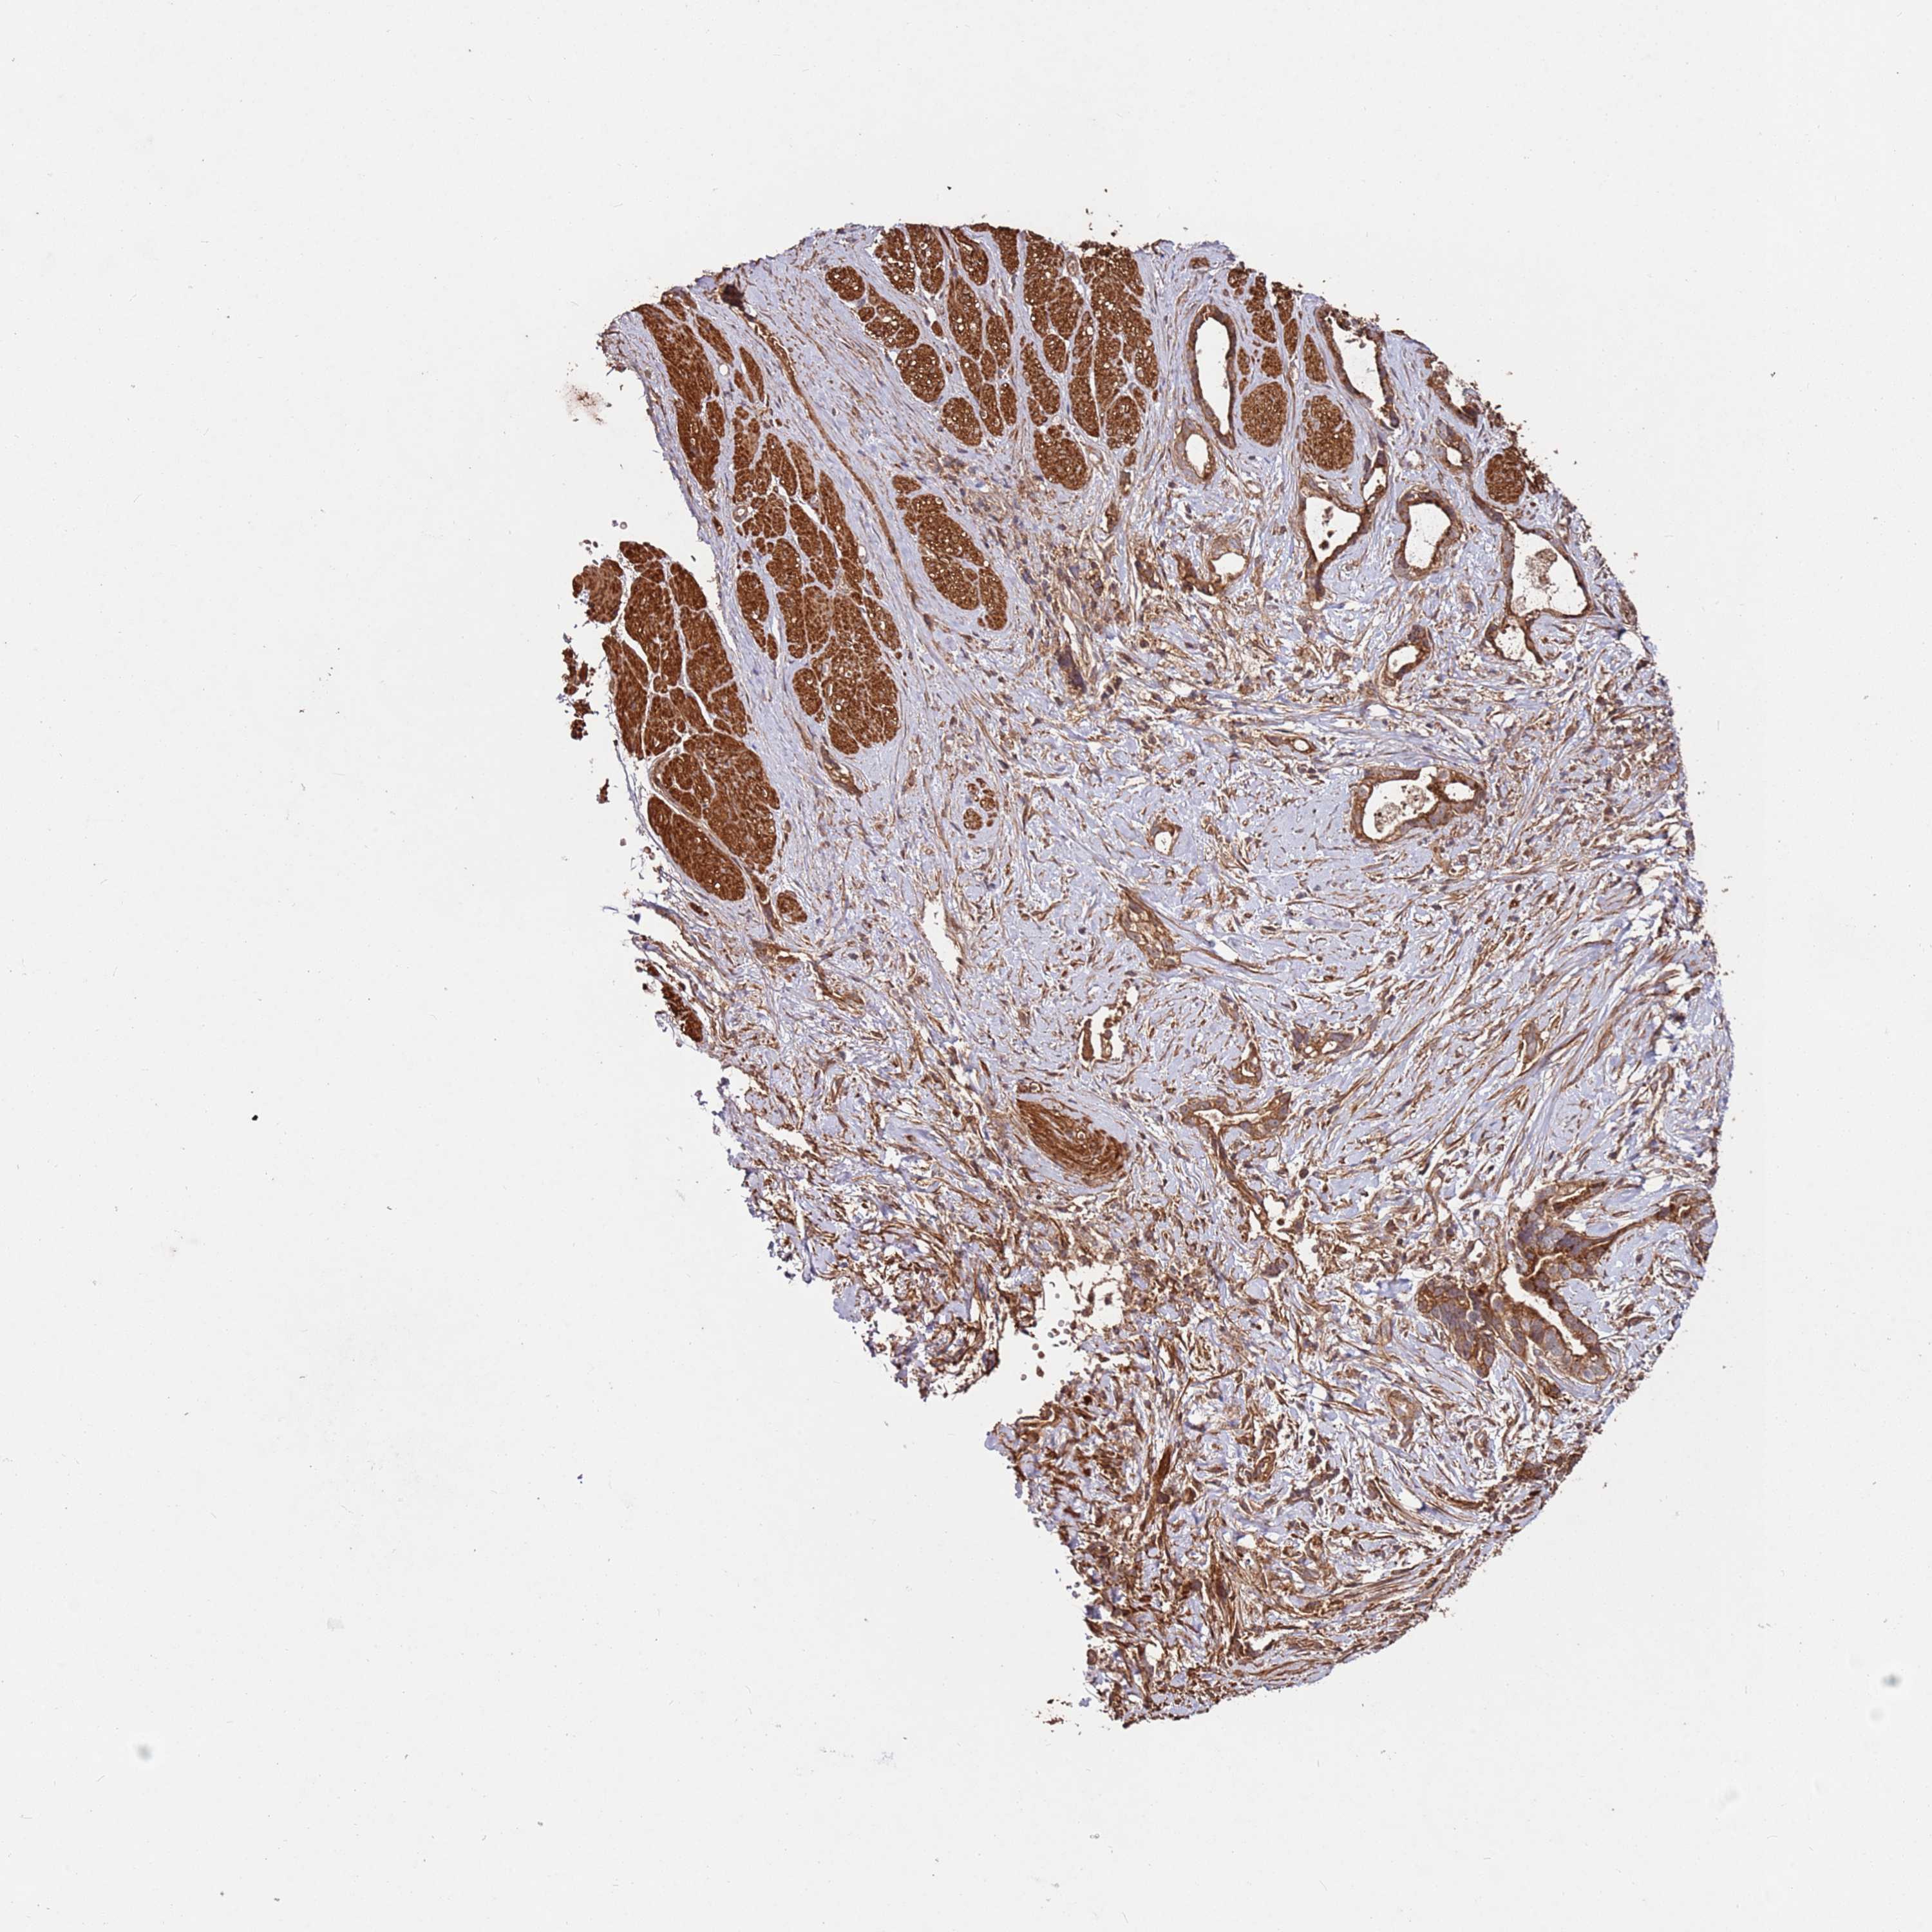

STOMACH CANCER - Protein expressioni

A mouse-over function shows sample information and annotation data. Click on an image to view it in a full screen mode. Samples can be filtered based on level of antibody staining by selecting one or several of the following categories: high, medium, low and not detected. The assay and annotation is described here.

Note that samples used for immunohistochemistry by the Human Protein Atlas do not correspond to samples in the TCGA dataset.

Antibody stainingi

Antibody staining in the annotated cell types in the current human tissue is reported as not detected, low, medium, or high, based on conventional immunohistochemistry profiling in selected tissues. This score is based on the combination of the staining intensity and fraction of stained cells.

Each image is clickable and will lead to virtual microscopy that enables deeper exploration of all samples and also displays staining intensity scores, fraction scores and subcellular localization as well as patient and tissue information for each sample.

Antibody HPA047128

Staining

High

Medium

Low

Not detected

Intensity

Strong

Moderate

Weak

Negative

Quantity

>75%

75%-25%

<25%

None

Location

Nuclear

Cytoplasmic/membranous

Cytoplasmic/membranous,nuclear

Adenocarcinoma, NOS